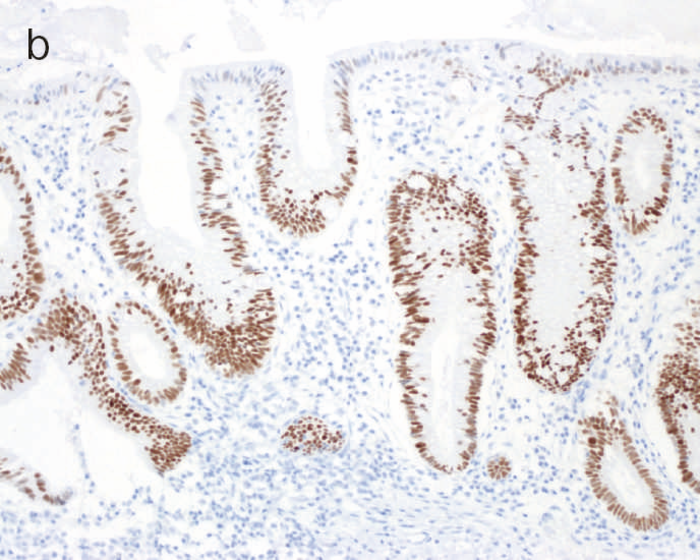

図10 Dysplasiaの多様な組織像

- 表層分化を示すdysplasia。

- 分泌顆粒の局在が核上,核下,表層と不規則な分布を示すdystrophic goblet cellを含むdysplasia。

dysplasiaはその異型度によりLGDとHGDに二分される(図9)。LGDは基本的に核の極性が比較的保たれており,表層への分化傾向がみられることを特徴とし,しばしば反応性異型との鑑別を要する。多彩な形態像を示すこともdysplasiaの特徴である。味岡らは,UC関連大腸腫瘍を5つの特殊なパターン(表層分化を示す分化型腺癌,分化細胞を豊富にもつ分化型腺癌,分化細胞に乏しい分化型腺癌,未分化型腺癌または分化型腺癌の脱分化,癌の判定が困難な分化型腫瘍)に分類し報告している3)。2019年に出版されたWHO分類には,IBDを背景に発生する粘膜内腫瘍をInflammatory bowel disease-associated dysplasia of the colorectumと呼称し,組織形態に基づき,intestinal(adenomatous)subtype,serrated subtype,mucinous type,a subtype with eosinophilic cytoplasm and marked goblet cell depletion,crypt cell subtypeやこれらの組織像が混在したmixed subtypeなどが存在すると記載されている4)(図10)。

このように多彩な像を呈するdysplasiaでは,特に異型度が低い場合に反応性異型との鑑別にしばしば難渋するが,dystrophic goblet cell,endocrine cell hyperplasia,Paneth細胞化生などの特徴的な上皮細胞分化異常を示す特殊な異型上皮の存在が形態学的な鑑別として有用である。また,dysplasiaでは,腫瘍発生早期の段階よりTP53遺伝子異常が起こることが知られている。したがって,上記の形態学的な異常とともに,免疫染色におけるp53蛋白異常発現の有無が反応性異型や散発性腺腫との鑑別において重要となる(TP53遺伝子変異が見られる際には,免疫染色においてp53蛋白過剰発現あるいは完全欠失を示すことが知られている)。これまでに,一般大腸腺腫・癌ではp53蛋白過剰発現はその異型度に相関するのに対し(腺腫で0.8~3.4%,低異型度癌で35.3%,高異型度癌で71.7%),dysplasiaでは低異型度の段階から高頻度(75%)にp53蛋白過剰発現を呈することが報告されている5)。したがって,特に低異型度腫瘍でp53蛋白異常発現パターンを示す場合はdysplasiaの可能性が高く,反応性異型との鑑別において診断的意義が高い。また,表層分化傾向を示すLGDではp53蛋白の過剰発現がある場合でも表層部ではp53蛋白の発現減弱がしばしば観察されるのに対し(unique basal patternと呼ばれる),HGDでは全層性にp53蛋白過剰発現を示すことが多い。Ki-67(増殖マーカー)染色では,dysplasiaでは細胞増殖帯が粘膜深層~中層に位置するが(bottom-up pattern),散発性腺腫では細胞増殖帯が腺管表層~中層に分布することが知られている(top-down pattern)。これらの免疫染色パターンは,dysplasiaと反応性異型や散発性腺腫との鑑別の際に重要な手がかりとなる(図9,図11)(CQ 12,CQ 13)。